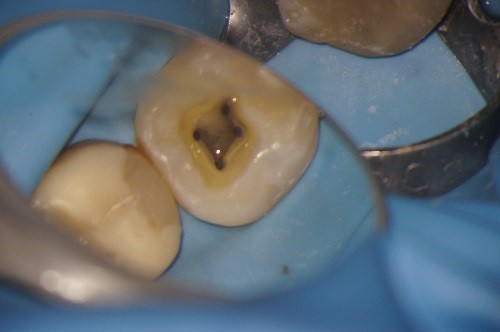

Hieronder ziet u de voortgang van een wortelkanaalbehandeling in zes foto’s..

Foto 2: De wortelkanalen zijn geprepareerd en klaar om uitgespoeld te worden.

Foto 3: De wortelkanalen worden uitgespoeld. Dit is het belangrijkste onderdeel van de wortelkanaalbehandeling.